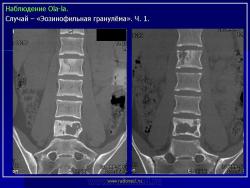

Продолжение.

1.gi_.slayd14.jpg2.gi_.slayd15.jpg3.gi_.slayd16.jpg1.gis_.slayd15.jpg2.gis_.slayd16.jpg3.gis_.slayd17.jpg4.gis_.slayd18.jpg5.gis_.slayd19.jpg6.gis_.slayd20.jpg7.gis_.slayd21.jpg8.gis_.slayd22.jpg9.gis_.slayd23.jpg